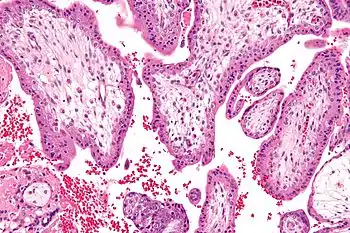

![]() Micrograph showing chorionic villi—the tissue that is collected in CVS. H&E stain. | |

Chorionic villus sampling (CVS), sometimes called "chorionic villous sampling" (as "villous" is the adjectival form of the word "villus"),[1] is a form of prenatal diagnosis done to determine chromosomal or genetic disorders in the fetus. It entails sampling of the chorionic villus (placental tissue) and testing it for chromosomal abnormalities, usually with FISH or PCR. CVS usually takes place at 10–12 weeks' gestation, earlier than amniocentesis or percutaneous umbilical cord blood sampling. It is the preferred technique before 15 weeks.[2][3]